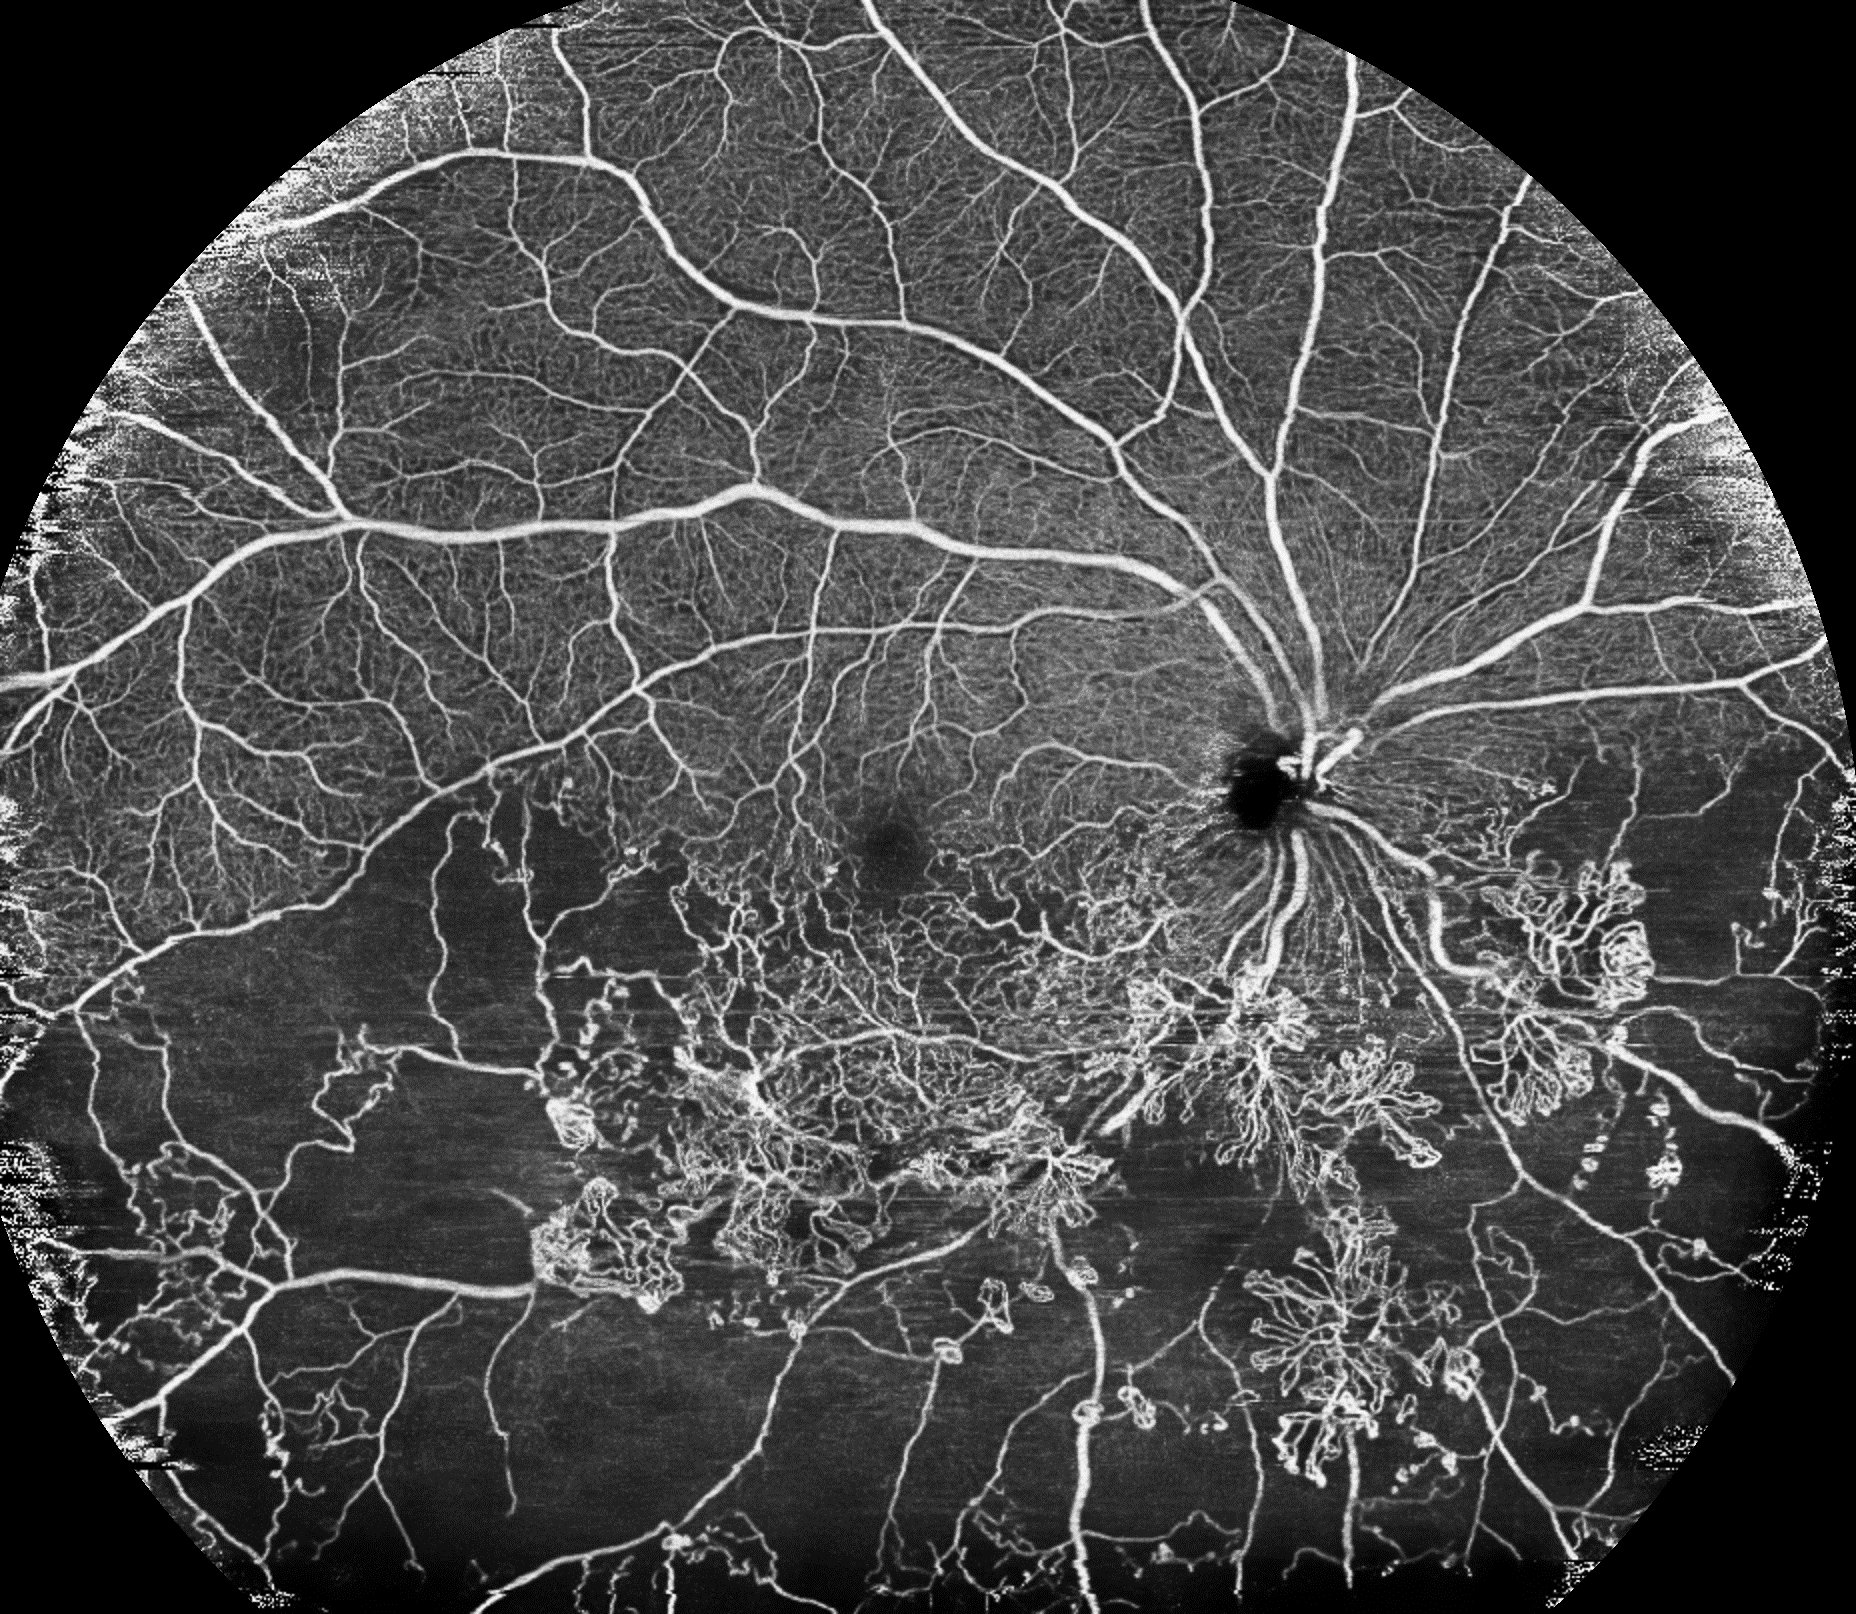

約80度の広角OCTA撮影により、一度の撮影で、糖尿病網膜症、動静脈閉塞症などの血管異常(無灌流領域や新生血管など)を確認することができ、従来のパノラマ撮影と比較して、被検者の負担が大きく軽減します。さらに、広角OCTAにも「Intelligent Denoise」を適用することで、広範囲でありながら、毛細血管の状態も確認できる高精細な画像取得を可能にしています。

毛細血管の状態も確認できる高精細な広角OCTA画像